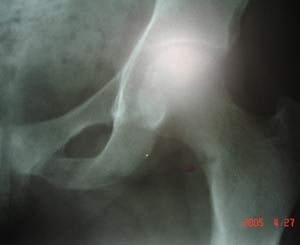

Femur neck revealin a minor fracture. It shows the bony trabeculae are interrupted across the fracture site. It may show step in the cortex.